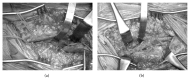

Cystic adventitial disease (CAD) is a rare cause of intermittent claudication and nonatherosclerotic conditions in middle-aged men without cardiovascular risk factors. The etiology of CAD is unclear; however, the direct communication between a cyst and a joint is presumed to be a cause. We herein report a case series of CAD of the popliteal artery (CADPA), in which patients were treated with surgical resection and vascular reconstruction. Although less invasive treatment modalities, including percutaneous cyst aspiration and percutaneous transluminal angioplasty, have been the subject of recent reports, these treatments have had a higher recurrence rate. Therefore, all of the CAPDA cases in the present series were treated surgically, which lead to good outcomes.